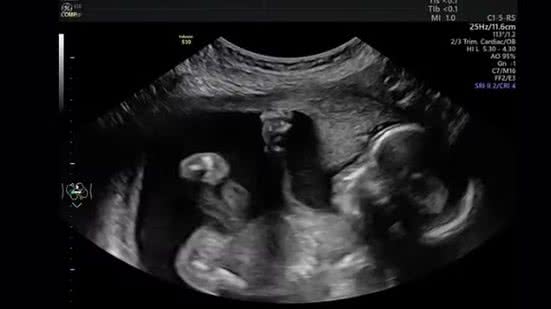

Durante um exame de ultrassom em Michigan, a mãe Mara McCoy e o pai Terrance McCoy capturaram um momento inusitado quando sua filha, Pyper, parecia dar um soco na barriga da mãe, gerando risadas no consultório e surpreendendo a todos.

O consultório médico em Michigan (EUA) explodiu em gargalhadas quando Mara McCoy estava sendo submetida a um exame de ultrassom na 20ª semana de gravidez, em setembro.

A cena pegou a todos de surpresa. Tudo transcorria normalmente até que Pyper resolveu se manifestar: a bebê foi vista "dando um soco" na barriga da mãe. A cena, capturada pelo pai, Terrance McCoy, parecia mostrar que a pequena estava se sentindo incomodada com o exame.

Embora o soco possa ter parecido "pessoal", os médicos dizem que movimentos fetais como golpes com as mãos, chutes e alongamentos são completamente normais nessa fase da gestação.